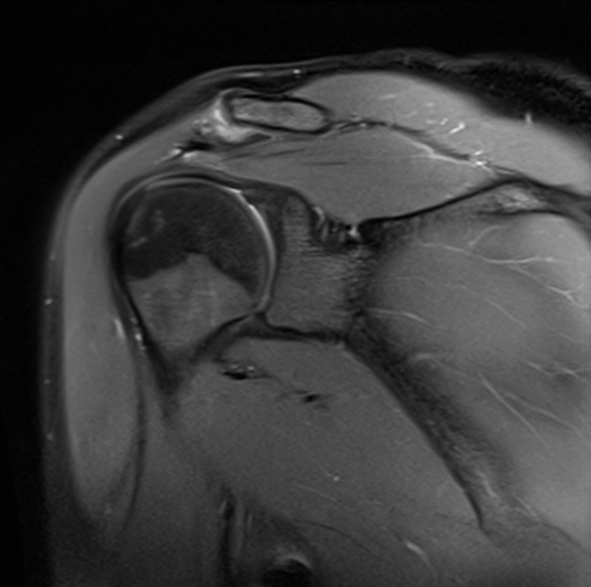

MRT Diagnose Schulter LabrumVerletzung (Schulterschmerzen)

Ein Riss des Labrum glenoidale verursacht Schmerzen bei der Bewegung. Die Behandlung erfolgt physiotherapeutisch und manchmal auch chirurgisch. Die Schulter ist, im Gegensatz zum Ellenbogen oder zur Hüfte, ein grundsätzlich instabiles Gelenk. Es wurde mit einem Golfball verglichen, der auf einem Abschlag-T liegt.

Das Labrum sorgt für Stabilität und Beweglichkeit der Schulter. Der Labrumabriss (Labrumläsion) oder auch SLAP-Läsion (die Abkürzung steht für "superiores Labrum von anterior nach posterior") ist eine klassische Schulterverletzung. Der Labrumabriss kann mit sich bringen, dass das Schultergelenk sich ohne Gewalteinwirkung von außen auskugelt.

Die Bankart-Läsion bezeichnet das teilweise oder vollständige Abreissen des Labrums im unteren, vorderen Bereich. Diese Verletzung entsteht häufig aufgrund einer Schultergelenksluxation, also dem „Auskugeln der Schulter". Ist auch das hintere Labrum abgerissen, spricht man von einer „reversed- Bankart- Läsion".